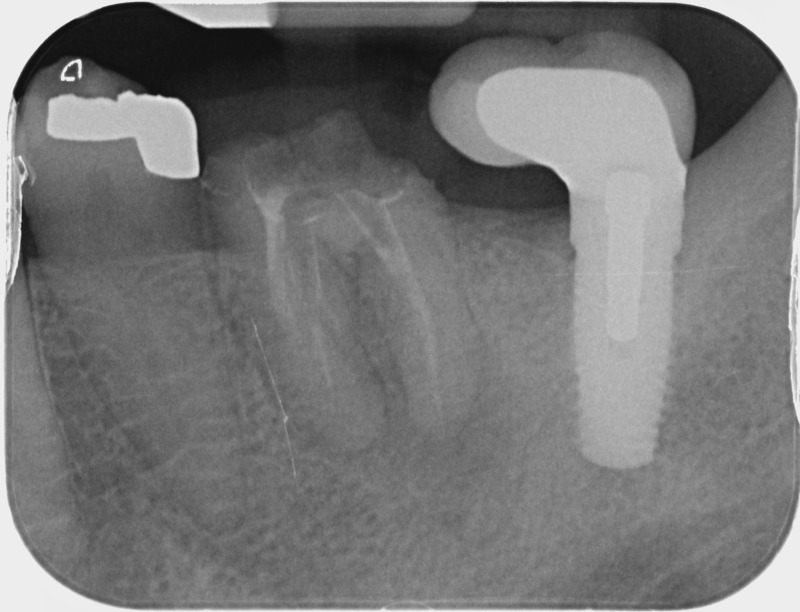

• Apexification : Chez le jeune enfant, une dent immature victime d’un traumatisme ou d’une carie volumineuse peut poser problème. Si la pulpe agressée se nécrose, alors la racine ne s’édifie plus et une lésion inflammatoire se développe au niveau osseux. L’apexification, par apposition d’un matériau biocompatible dans la racine, cherche à induire la formation d’une barrière artificielle à l’extrémité de celle-ci, et permettre la cicatrisation de la lésion dans le but de maintenir la dent en bouche à long terme.

Avant

Après